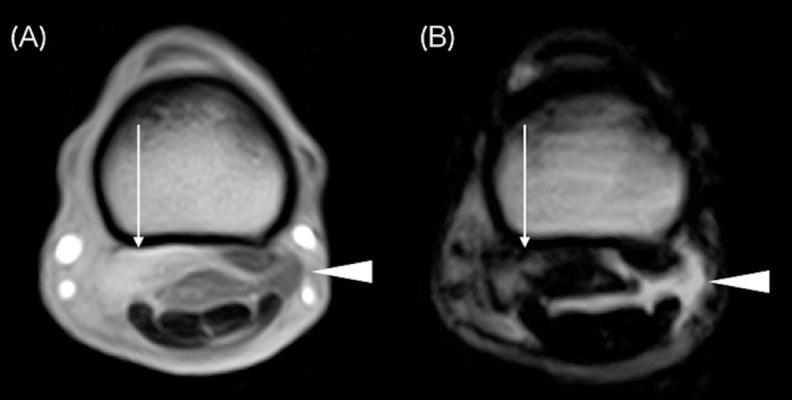

Desmitis of the oblique distal sesamoidean ligaments (ODSL) is caused by hyperextension of the metacarpophalangeal/metatarsophalangeal joint and has been described as a significant cause of lameness in racehorses. In this study, three Thoroughbred racehorses (age range: 3-6 years) were diagnosed with desmitis of the forelimb ODSL using standing low-field magnetic resonance imaging (sMRI). Radiography and ultrasonography were inconclusive with regard to a definitive diagnosis. For all horses, the sMRI characteristics included increased signal intensity within the medial ODSL on T1-weighted gradient echo, T2-weighted fast spin echo and short tau inversion recovery fast spin echo images, which use a fat suppression technique. Effusion of the digital flexor tendon sheath was also clearly visible on sMRI. Following rest and controlled exercise for roughly 3 months, two horses successfully returned to racing within 5 months. Our findings support the use of sMRI for diagnosing ODSL injuries in Thoroughbred racehorses.

斜方远籽骨韧带(ODSL)炎是由掌指关节/跖趾关节过度伸展引起的,已被描述为赛马跛行的一个重要原因。在本研究中,使用站立式低场磁共振成像(sMRI)对3匹纯种赛马(年龄范围:3至6岁)进行了前肢ODSL炎的诊断。X线摄影和超声检查对于明确诊断尚无定论。对于所有马匹,sMRI特征包括在使用脂肪抑制技术的T1加权梯度回波、T2加权快速自旋回波和短tau反转恢复快速自旋回波图像上,内侧ODSL内信号强度增加。在sMRI上也清晰可见指屈肌腱鞘积液。经过大约3个月的休息和控制运动后,两匹马在5个月内成功重返赛场。我们的研究结果支持使用sMRI诊断纯种赛马的ODSL损伤。